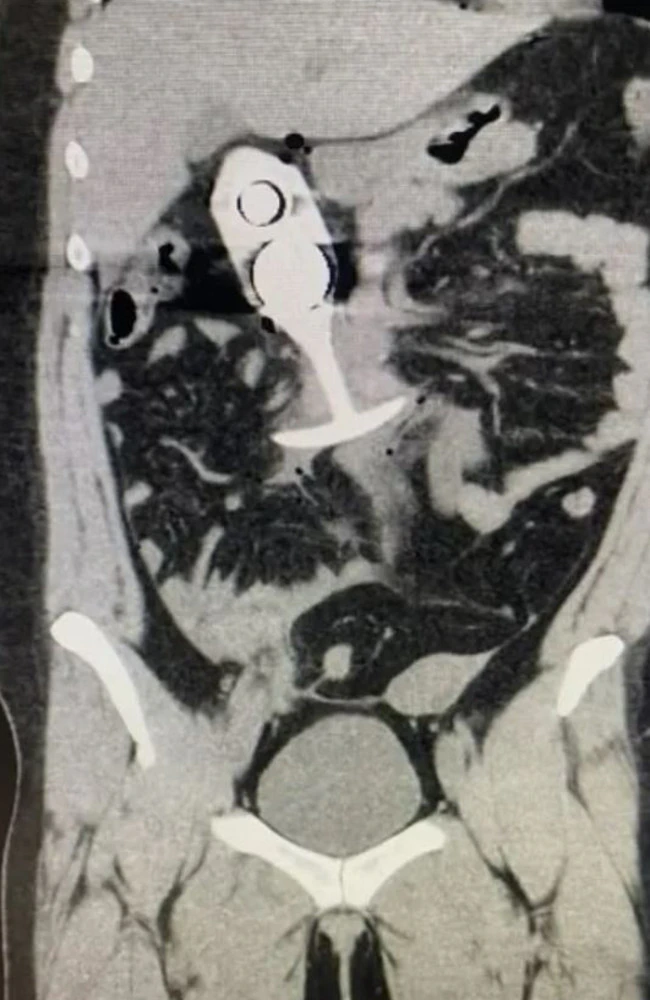

Rump Rocket

So ,, a 23 yo Australian woman goes in for an MRI scan , they tell her that she cannot have any meta..